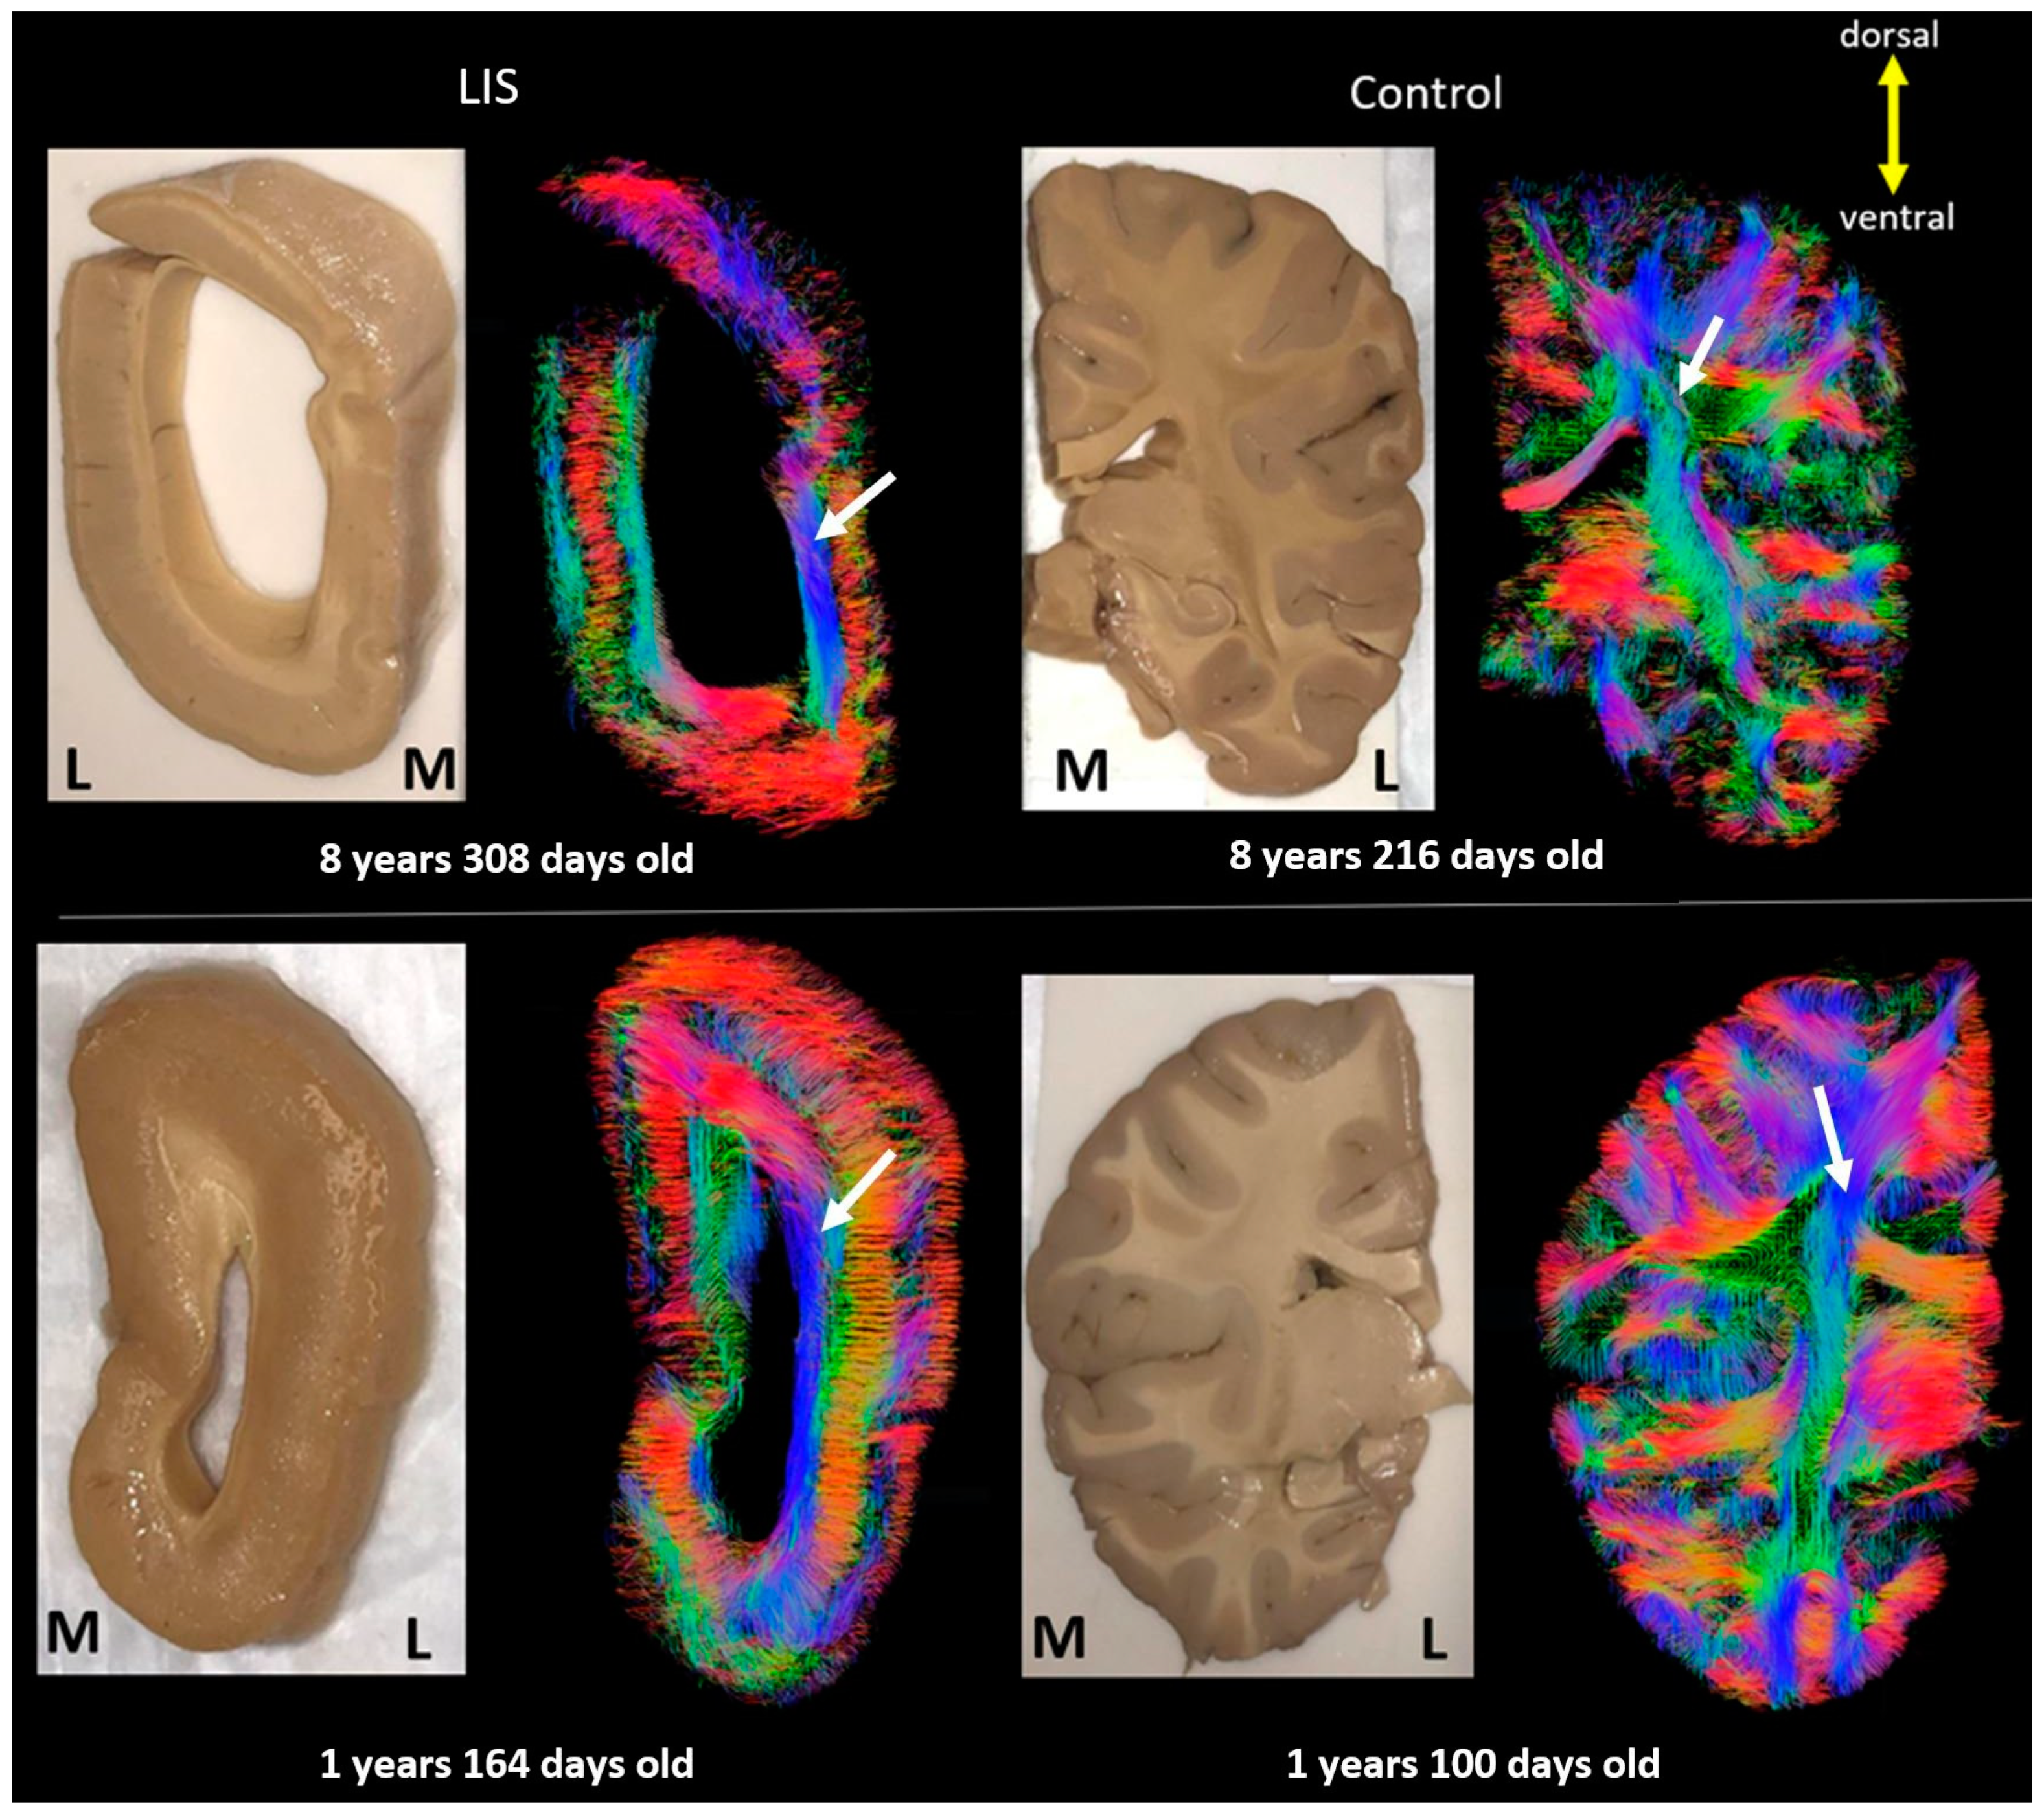

3. Results

4. Discussion

4.1. Developmental Aspect of the LIS Brains

4.2. Microanatomy of Lissencephaly